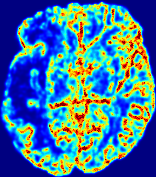

LesionRefer to captionRefer to captionRefer to captionRefer to captionRefer to captionRefer to caption𝐕rgbsubscript𝐕𝑟𝑔𝑏{\bf{V}}_{rgb}Refer to captionRefer to captionRefer to captionRefer to captionRefer to captionRefer to caption𝐕2subscriptnorm𝐕2{\|\bf{V}}\|_{2}Refer to captionRefer to captionRefer to captionRefer to captionRefer to captionRefer to captionRefer to caption3.53.53.52.82.82.82.12.12.11.41.41.40.70.70.70.00.00.0(mm/s)𝑚𝑚𝑠(mm/s)D𝐷DRefer to captionRefer to captionRefer to captionRefer to captionRefer to captionRefer to captionRefer to caption0.0200.0200.0200.0160.0160.0160.0120.0120.0120.0080.0080.0080.0040.0040.0040.0000.0000.000(mm2/s)𝑚superscript𝑚2𝑠(mm^{2}/s)Slice #1Slice #2Slice #3Slice #4Slice #5Slice #6

Figure 4: PIANO feature maps for another patient in the ISLES 2017 training set, where the lesion is located in the right hemisphere. Top row: segmented stroke lesion region (white) on different slices. The corresponding slices for the PIANO feature maps are shown in the following rows.

For a better insight into an estimated velocity field 𝐕𝐕{\bf{V}} and diffusion field 𝐃𝐃{\bf{D}}, we compute the following maps: (1) 𝐕rgbsubscript𝐕𝑟𝑔𝑏{\bf{V}}_{rgb}: Color-coded orientation map of 𝐕=(Vx,Vy,Vz)T𝐕superscriptsuperscript𝑉𝑥superscript𝑉𝑦superscript𝑉𝑧𝑇{\bf{V}}=(V^{x},V^{y},V^{z})^{T}, obtained by normalizing 𝐕𝐕{\bf{V}} to unit length and mapping its 3 components to red, green, blue respectively; (2) 𝐕2subscriptnorm𝐕2\|{\bf{V}}\|_{2}: 222 norm of 𝐕𝐕{\bf{V}}; (3) D𝐷D: scalar field in Eq. 5.

Fig. 3 and Fig. 4 show the PIANO feature maps estimated from two ISLES 2017 patients: all are highly consistent with the lesion in both cases. Details of the blood flow trajectories are revealed in 𝐕rgbsubscript𝐕𝑟𝑔𝑏{\bf{V}}_{rgb} by the ridged patterns and the sharp changes of colors in the unaffected (right) hemisphere, while the flat patterns appearing within the lesion provide little directional information about the velocity and indicate low velocity magnitudes. Velocity magnitudes are more directly visualized via 𝐕2subscriptnorm𝐕2\|{\bf{V}}\|_{2}, from which one can easily locate the lesion where 𝐕2subscriptnorm𝐕2\|{\bf{V}}\|_{2} is low. D𝐷D also indicates lower diffusion values in the lesion, though with less contrast potentially due to the fact that it captures the accumulated effect of CA diffusion at the voxel-level.